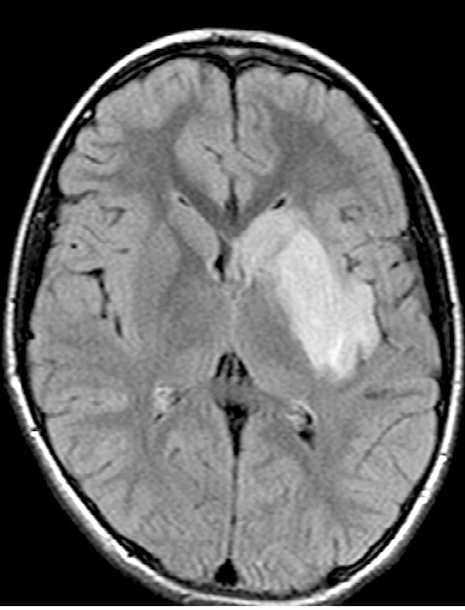

Après différents examens bactériologiques et hématologiques, un scanner pulmonaire low dose ne montre aucun signe pathologique. Au Doppler couleur, les carotides sont normales ainsi que l'échocardiographie. Mais l’IRM cérébrale montre des résultats compatibles avec un infarctus aigu sans microhémorragies, ainsi qu'un rétrécissement irrégulier du segment M1 proximal de l'artère cérébrale moyenne gauche avec un flux distal légèrement réduit.

On distingue également une image hyperdense en T2 FLAIR au niveau des noyaux gris centraux gauches et un infarctus aigu de l'insula. Il existe de nombreuses considérations différentielles potentielles chez un enfant victime d'un AVC aigu, embolique ou thrombotique, la vasculite cérébrale dans le contexte d'une maladie systémique (par exemple pour la maladie de Kawasaki) notamment. Notre principal diagnostic est l’artériopathie focale cérébrale, l'une des causes les plus courantes d'AVC ischémique artériel chez l'enfant, qui est définie comme une "sténose / irrégularité unifocale et unilatérale des grandes artères intracrâniennes de la circulation antérieure".